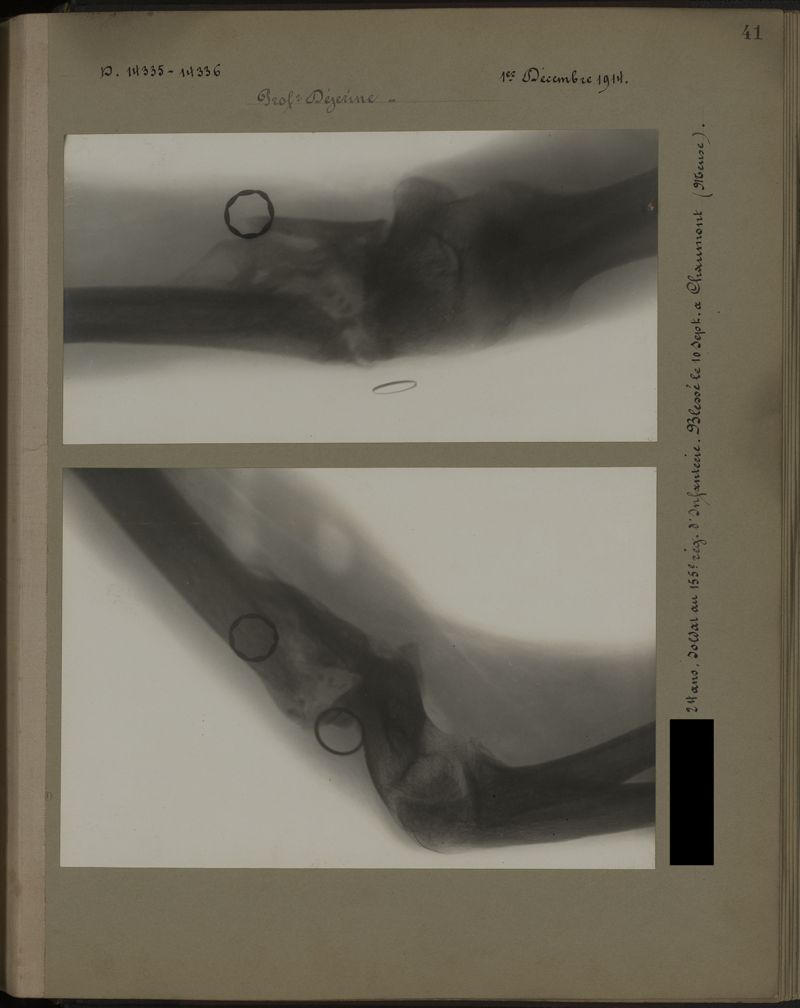

Deux albums de radiographies de la Première Guerre mondiale. Collection du laboratoire central de radiographie de la Salpêtrière. Deuxième album.

1915.